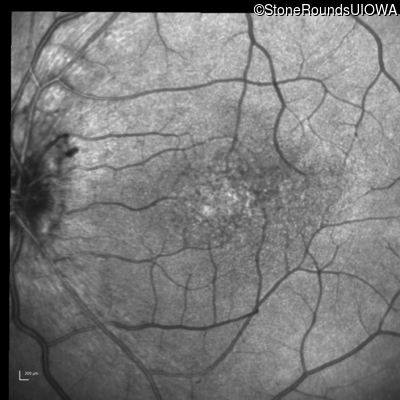

Infrared Fundus Photograph - Right - 20/30 -2

Exemplar